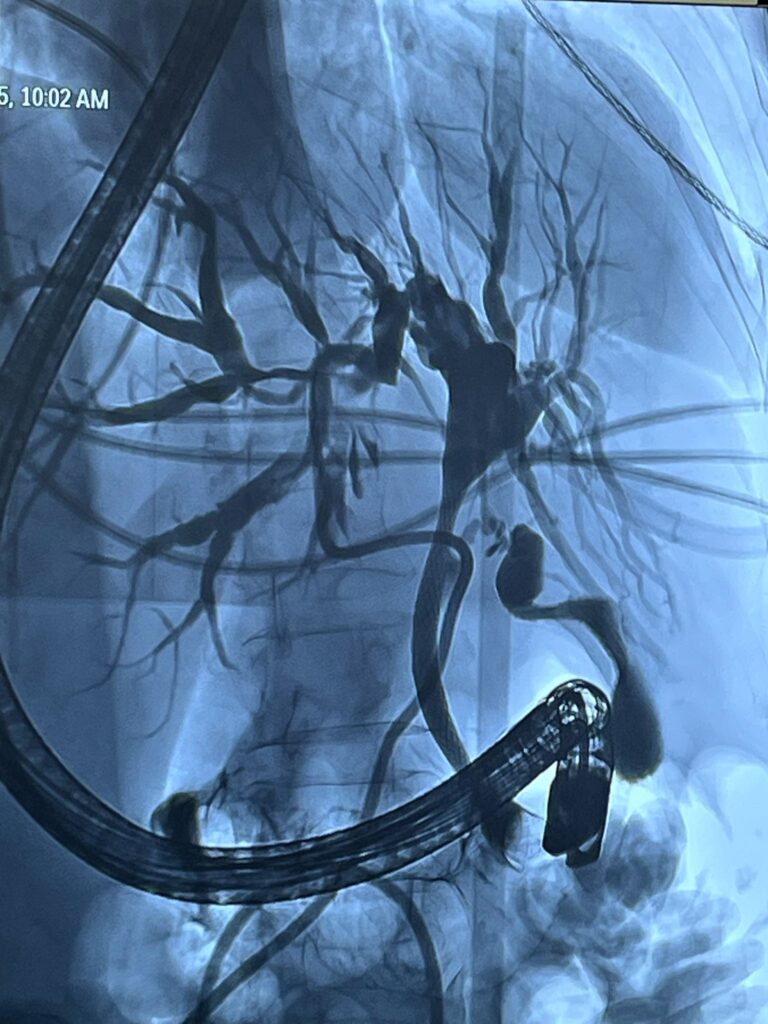

Pacienta, în vârstă de 71 de ani, cu colestază severă cauzată de o formațiune tumorală situată la nivelul hilului hepatic, a beneficiat de o abordare terapeutică multidisciplinară în două etape, în contextul unui caz considerat inoperabil chirurgical.

În prima etapă, echipa de Radiologie Intervențională a realizat cu succes un drenaj biliar percutan transhepatic. Ulterior, în a doua etapă, în colaborare cu echipa de Gastroenterologie, s-a efectuat montarea unui stent pe căile biliare extrahepatice, printr-o procedură hibridă, ghidată atât angiografic, cât și endoscopic.

Această intervenție a fost posibilă datorită dotării spitalului cu angiograful utilizat în cadrul procedurii, achiziționat printr-un proiect coordonat de dr. Florin Grosu, cu sprijinul și efortul financiar al Consiliului Județean Sibiu.